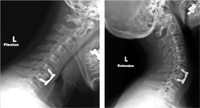

Fig. 1 Surgical technique including four steps:

discectomy and distraction of the interbody space (A),

microsurgical decompression (B), trial spacer for graft

choice(c), and insertion of interbody

polyetheretherketone (PEEK) cage (D).